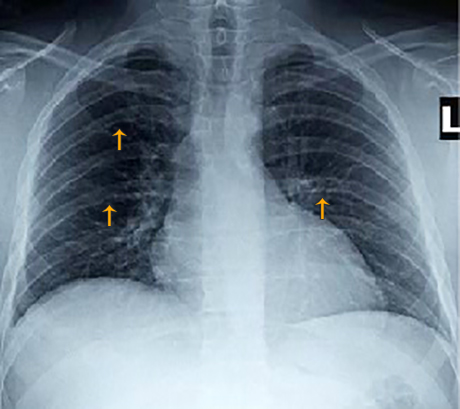

Chest X rays provide additional useful information in our patient, particularly prior to considering treatment of his abnormality.

Choose the best interpretation of the abnormality indicated by the arrows in our patient's chest X ray: